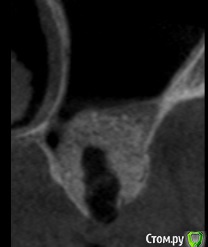

Andre_ Опубликовано 14 июня, 2018 Поделиться Опубликовано 14 июня, 2018 ... в чём дело, сразу не поймёшь.Добрый всем день. Выполнен открытый синус - лифтинг с Bio-Oss, исходно в области альвеолярного отростка высота своей кости 2-3 мм, через 6 месяцев - имплантация без особенностей, ложе умеренно кровило. Гранулы на сверле были, но встали имплантаты с торком порядка 20 Н/см2. Раскрытие спустя 3 мес., имплантаты на фдм выкручены рукой. Ложа откюретированы, заполнены коллагеном и ушиты, спустя 5 суток жалобы на боли - искомая область абсцедирует. Разрез, гной и крупицы, стенки и дно ложа винтов при зондировании инструментом таки твёрдые. Назначены а\б повторно, и загружены фото с контрольной КТ. Где, по- вашему, допустио ошибку и какую? И каков прогноз на переустановку? Столкнулся с такой проблемой впервые и немного дезориентировался. Ссылка на комментарий

TIGER Опубликовано 20 июня, 2018 Поделиться Опубликовано 20 июня, 2018 ... в чём дело, сразу не поймёшь.Добрый всем день. Выполнен открытый синус - лифтинг с Bio-Oss, исходно в области альвеолярного отростка высота своей кости 2-3 мм, через 6 месяцев - имплантация без особенностей, ложе умеренно кровило. Гранулы на сверле были, но встали имплантаты с торком порядка 20 Н/см2. Раскрытие спустя 3 мес., имплантаты на фдм выкручены рукой. Ложа откюретированы, заполнены коллагеном и ушиты, спустя 5 суток жалобы на боли - искомая область абсцедирует. Разрез, гной и крупицы, стенки и дно ложа винтов при зондировании инструментом таки твёрдые. Назначены а\б повторно, и загружены фото с контрольной КТ. Где, по- вашему, допустио ошибку и какую? И каков прогноз на переустановку? Столкнулся с такой проблемой впервые и немного дезориентировался. sav1.jpg sav2.jpg sav3.jpgСверлили под импланты по полному протоколу? Ссылка на комментарий